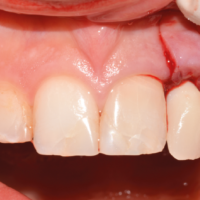

La nostra paziente è una ragazza di ventidue anni, trattata ortodonticamente presso uno studio privato, che si rivolge a noi per sostituire un ponte Maryland, che maschera l’agenesia di un incisivo laterale superiore di sinistra. Da un esame obiettivo iniziale, crediamo che ci siano le condizioni per costruire una corona che rispetti i rapporti dento-dentali con gli elementi contigui (Figg. 1, 2).

- Fig. 1

- Fig. 2